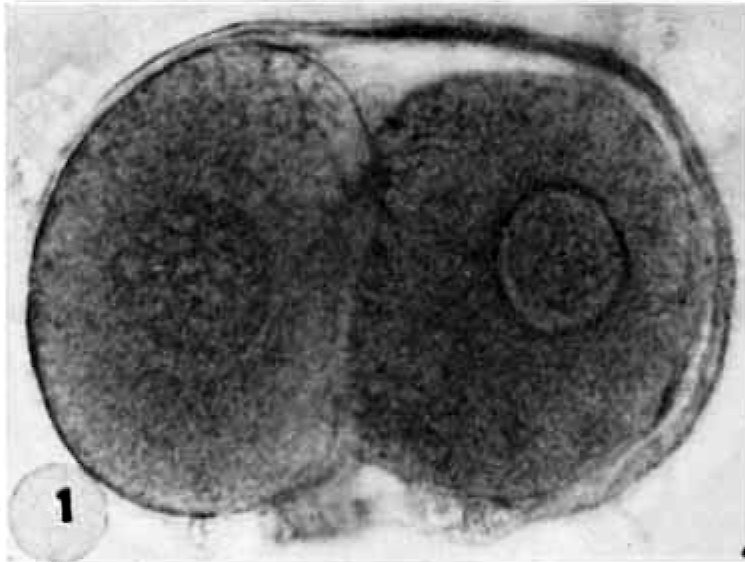

Zygote

A fertilized, diploid single-celled egg

4 - DNA replication of male and female pronucleus that fuse to form a diploid zygote that initiates mitosis to form a 2-celled embryo

Pronuclear Stage

Zygote approximately 12 to 15 hours after fertilization (human).

Cleavage

Repeated mitotic divisions during week one of embryonic development (days 0-4) that occurs as the conceptus migrates down the uterine tube.

Day 0 - Pronuclear stage

Day 1 - Cleavage begins, 2-cell stage